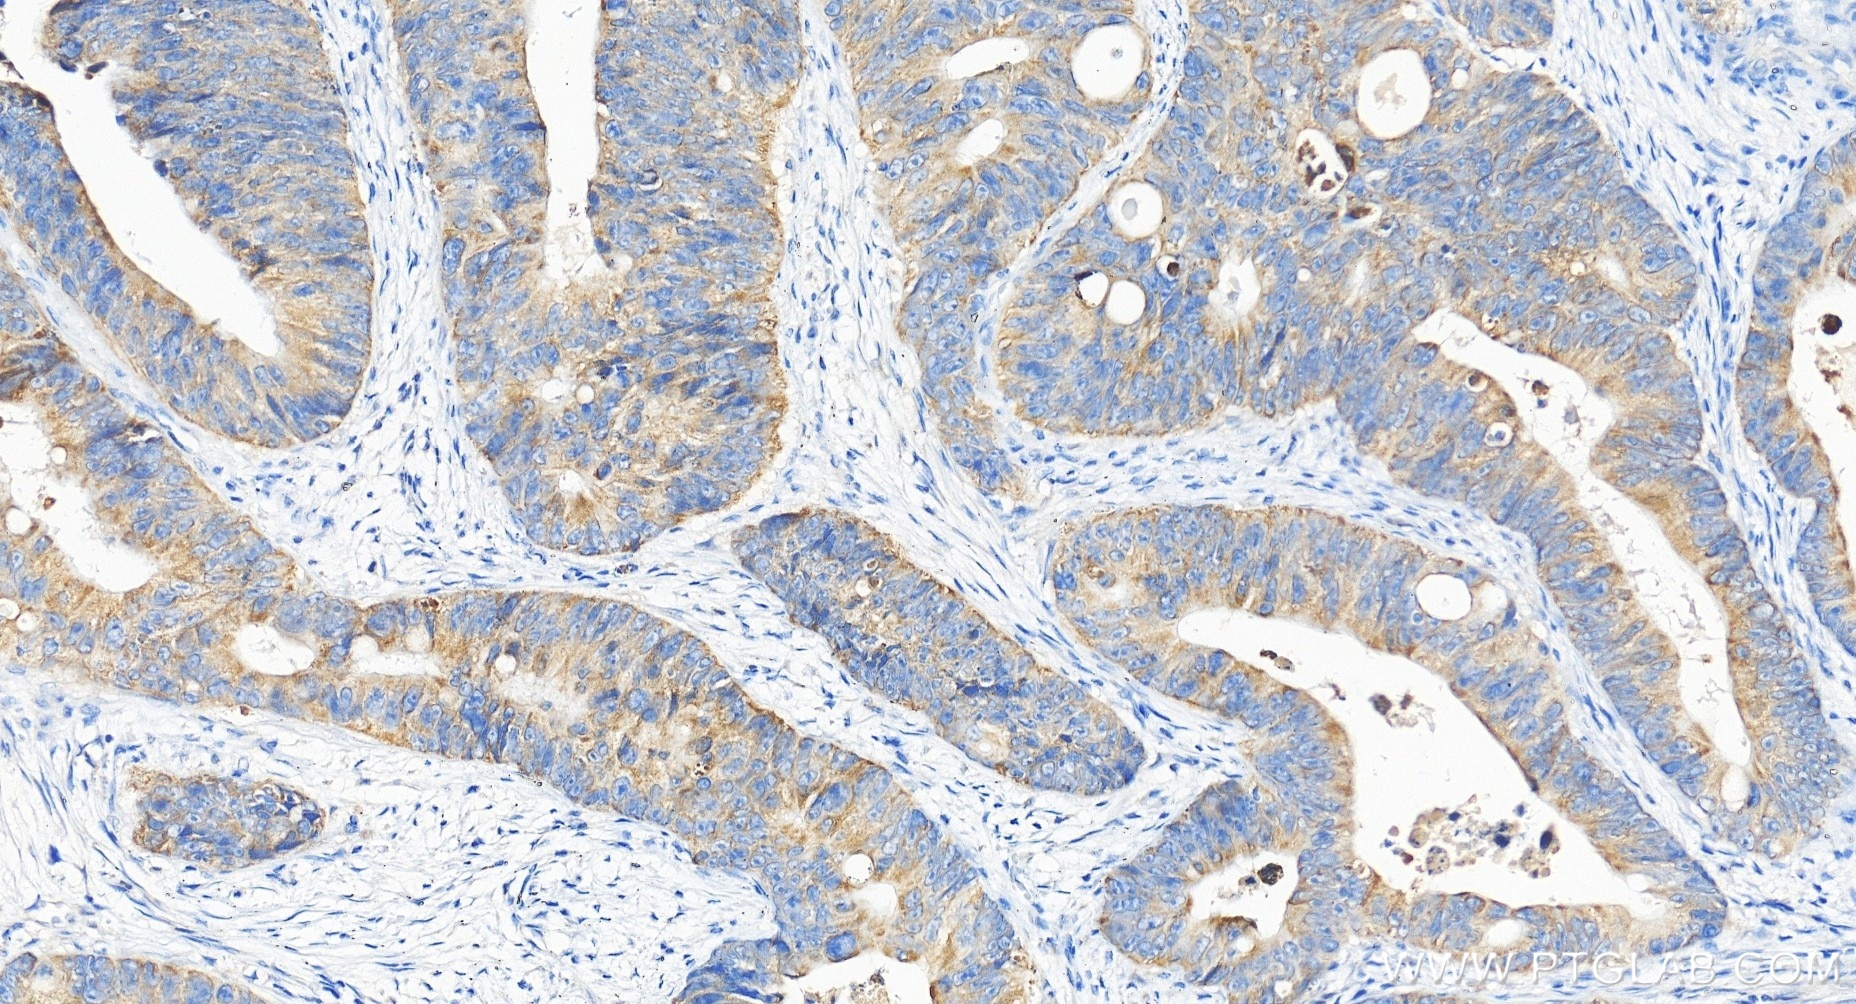

| Positive IHC detected in | human colon cancer tissue Note: suggested antigen retrieval with TE buffer pH 9.0; (*) Alternatively, antigen retrieval may be performed with citrate buffer pH 6.0 |

| Immunohistochemistry (IHC) | IHC : 1:50-1:500 |